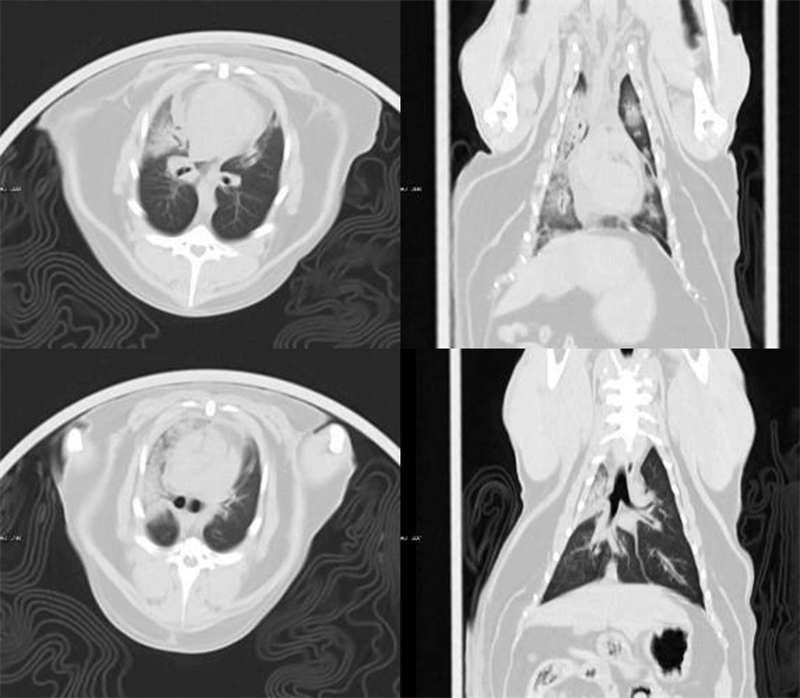

VetCare CT | 16 & 32 slices

VetCare CT features specially designed protocols for vet scans with highlights of self-explanatory workflow and tailored solutions for various pets. On top of the user-friendly protocols, MinFound provides professional hands-on operation training and 24-hour technical service.